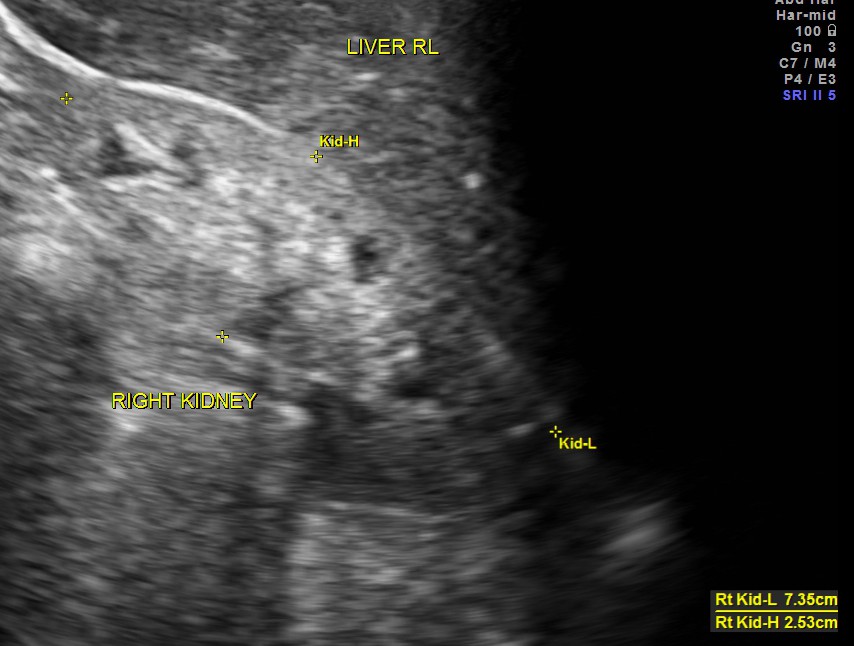

Both kidneys show features of medical renal disease.